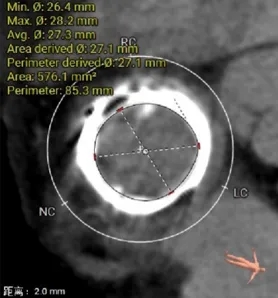

瓣架内径:25.0mm

瓣架外径:28.7mm

心室侧2mm:24.1mm

心室侧4mm:24.1mm

心室侧6mm:23.9mm

心室侧10mm:23.0mm

左房侧少量钙化

瓣架高度:约17.0mm

选瓣依据:该二尖瓣原置换生物瓣型号未知,CT测量生物瓣瓣环周长折算直径约25.0mm,瓣架高度约17mm。